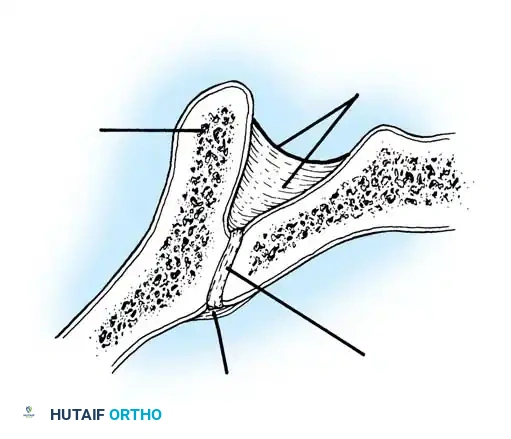

The Moe Technique (Lumbar Spine)

In the lumbar spine, the facet joints are oriented in a more sagittal plane, necessitating a modified approach.

Fig. 38-27: The Moe technique adapted for lumbar facet fusion, addressing the sagittal orientation of the joints.

- Utilize a small osteotome or a needle-nose rongeur to resect the adjoining joint surfaces.

- This creates a distinct rectangular defect within the sagittally oriented joint space.

- Pack this defect forcefully with cancellous bone graft.

- Proceed to decorticate the entire exposed posterior elements (laminae and transverse processes) using Cobb gouges, always directing force away from the spinal canal.